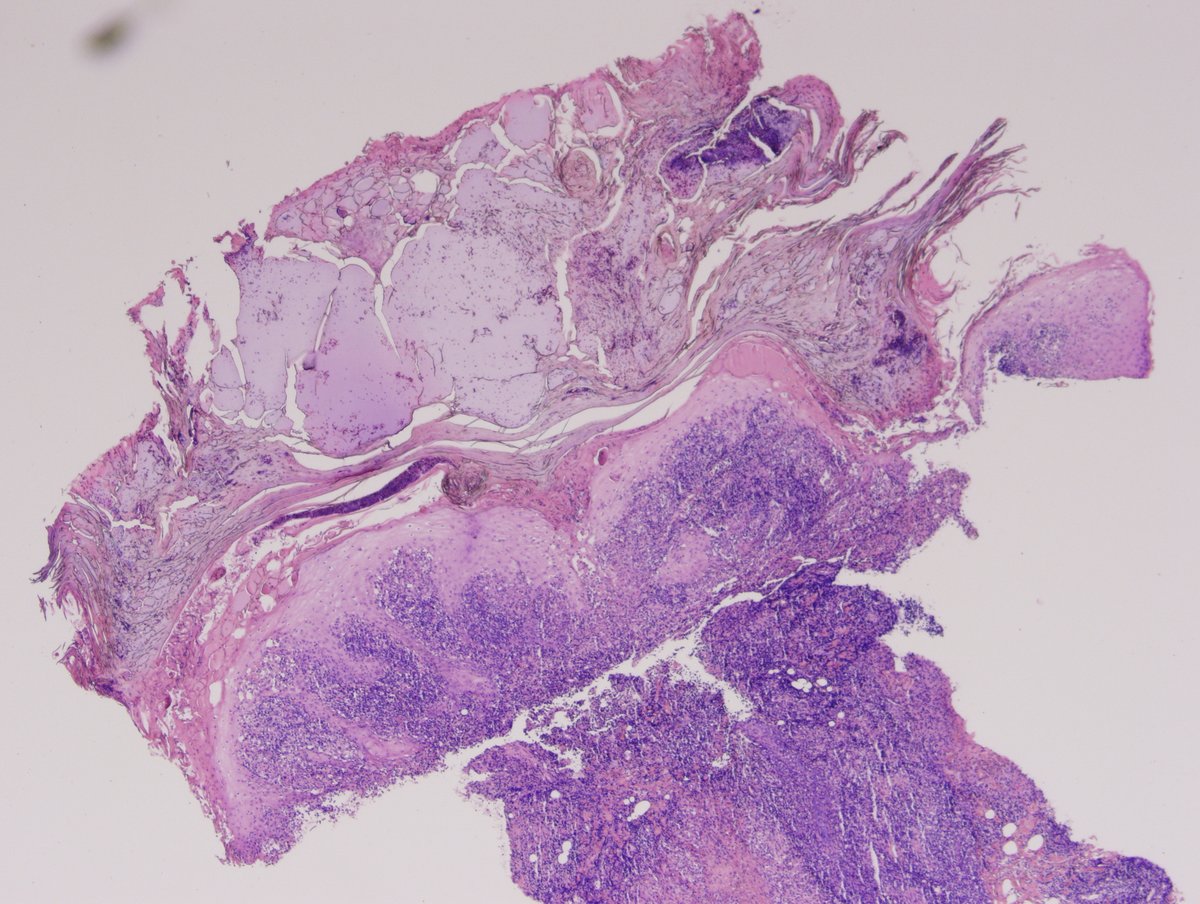

It's beautiful when tumors read the book. Gastric body mass. When autoimmune gastritis meets well-differentiated NET.

#GIpath#pathology pic.twitter.com/67Qbxob19d